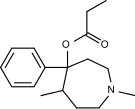

Pirinitramides

Structures

| Pirinitramides | ||||

|---|---|---|---|---|

|

| |||